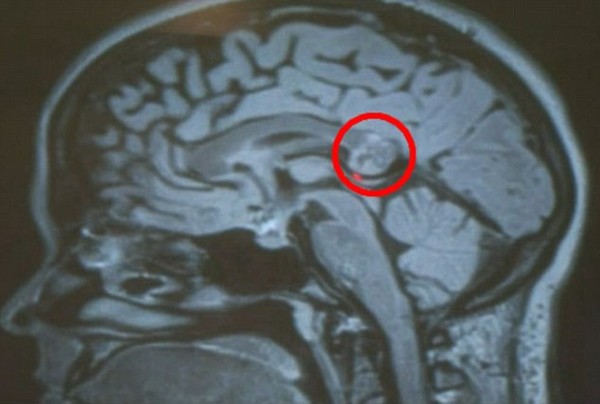

Các bác sỹ đã không thể tin nổi vào mắt mình khi nhìn thấy trong não của cô gái 26 tuổi có một khối u hình thành đầy đủ xương, tóc và răng như người trưởng thành. Nhiều người nghĩ đây là bào thai ác quỷ đã tồn tại trong não cô gái!

Đó là trường hợp của Yamini Karanam, cô gái 26 tuổi sống ở bang Indiana, Mỹ. Khi đến bệnh viện kiểm tra về tình trạng chậm đọc hiểu và giao tiếp hồi tháng 9/2014, Yamini cho biết, nếu có vài người trong phòng nói chuyện, cô sẽ không thể hiểu được họ đang nói gì. Thời điểm đó các bác sĩ không thể xác định rõ được bệnh tình của cô sinh viên này cho tới khi tiến hành phẫu thuật qua một lỗ nhỏ trên hộp sọ. Họ phát hiện ra khối u nằm bên trong não bộ chính là bào thai người chị em song sinh không thể phát triển hoàn thiện và đã chết của Yamini.

Hình chụp X-quang não bộ của Yamini.

Trường hợp song sinh sống ký sinh của Yamini Karanam, cô gái trẻ 26 tuổi, người Mỹ đã gây sốc cho các bác sĩ tại bệnh viện nơi cô điều trị khi họ phát hiện ra trong não bộ của cô có một khối u hình thành đầy đủ xương, tóc và răng như con người.

Yamini Karanam, 26 tuổi bị bào thai của chị em song sinh nằm chèn trong não.

Với cấu trúc xương, răng và tóc đã hình thành đầy đủ, khối u này trong thuật ngữ y học được gọi là u quái. Bác sĩ Hrayr Shahinian, Học viện nghiên cứu Hộp sọ tại Los Angeles cho biết, trong số 8.000 ca u não mà ông từng tiếp nhận, đây mới là ca u quái thứ hai mà ông gặp phải.

Sau khi được điều trị Yamini đã dần hồi phục sức khỏe sau ca phẫu thuật.